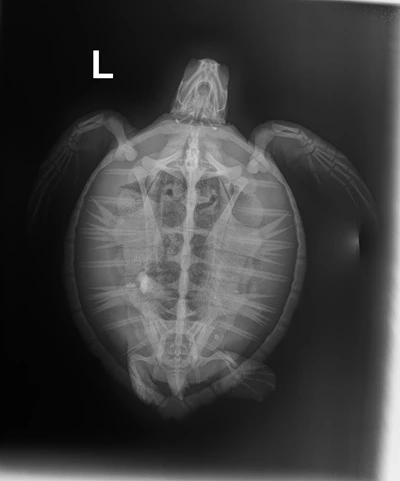

2.10 kg juvenile Atlantic Green sea turtle

External Wounds: Healed wound on the shoulder of the left front flipper with exudate on it. Small abrasion the ventral side of the left front flipper. Minor abrasions on the belly and shell.